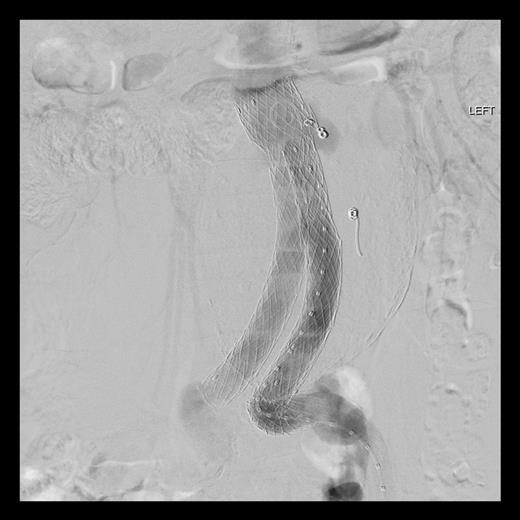

An 81-year-old gentleman with a background of ischaemic heart disease, hypertension, hyperlipidaemia, polycystic kidney disease and previous right hemicolectomy for bleeding diverticular disease, underwent EVAR 10 years ago. He was on yearly follow-up with computed tomography (CT) scan and latest CT in 2012 showed a type III endoleak with aneurysmal sac of 10 cm in size. Both common iliac arteries were long and tortuous. He was electively admitted for a diagnostic calibrating aortogram in our CT hybrid angiography suite (Toshiba Infinix VC-i). Intra-operatively, digital subtraction angiography (Fig. 1) showed significant type IIIa endoleak with component separation on the left iliac limb. The old stent graft was <20 mm away from the left renal artery proximally (lowest visceral artery). He was discharged the next day and re-admitted 2 weeks later for a staged operation. Decision was made for a combination of left renal artery chimney, aortouniiliac stent grafting and femorofemoral crossover bypass.

Digital subtraction angiography showing significant type 3a endoleak with component separationon the left iliac limb (black arrow). Both common iliac arteries were long and tortuous.